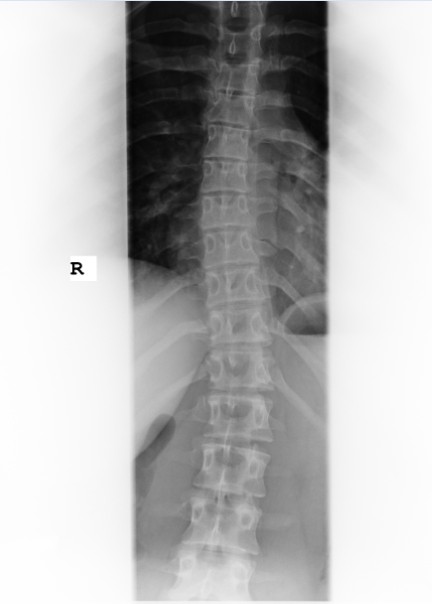

ich hab vorhin noch ne Weile in verschiedenen Threads gelesen und mir noch mal Yasmins Bild vorgeknöpft.

Ich habs Bild jetzt mal abfotografiert und hoffe das es in der 30KB Qualität noch gut zu erkennen ist.

Mit dem anhängen hat es nun geklappt.

Gruß Jaelle

- jassi1.jpg (26.8 KiB) 11326 mal betrachtet

deine Tochter hat keine sooo starke Krümmung, allerdings zu viel, um unbehandelt zu bleiben. Schwer zu sagen, ob die Ausbildung das richtige für sie sein wird. Hat sie in dem Bereich schon Praktikum gemacht? Muss sie darin z.B. viel in gebückter Haltung arbeiten? Was sagt der Arzt, der für die Ausbildung die Jugendschutz-Untersuchung durchgeführt hat?

Also es sind ja lumbal nur ca. 20°, thorakal noch etwas weniger. Thorakal ist auch keine Rotation zu erkennen, lumbal wäre das wohl Grad 1 von 4 nach Nash/Moe.

Ich denke viele hier im Forum wären froh, wenn sie so ein Röntgenbild hätten

Es ist aber nicht ausgeschlossen, dass es sich noch verschlechtern kann.

Das Röntgenbild sieht aber nicht nach einer gravierenden Skoliose aus. Auch würde ich deswegen nicht sofort die Ausbildung wieder absagen.